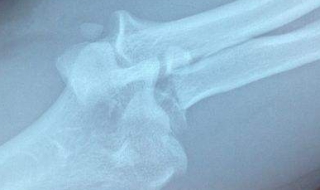

骨裂怎么办 肋骨骨裂怎么办

1、饮食疗法2、药物疗法3、维生素D和钙